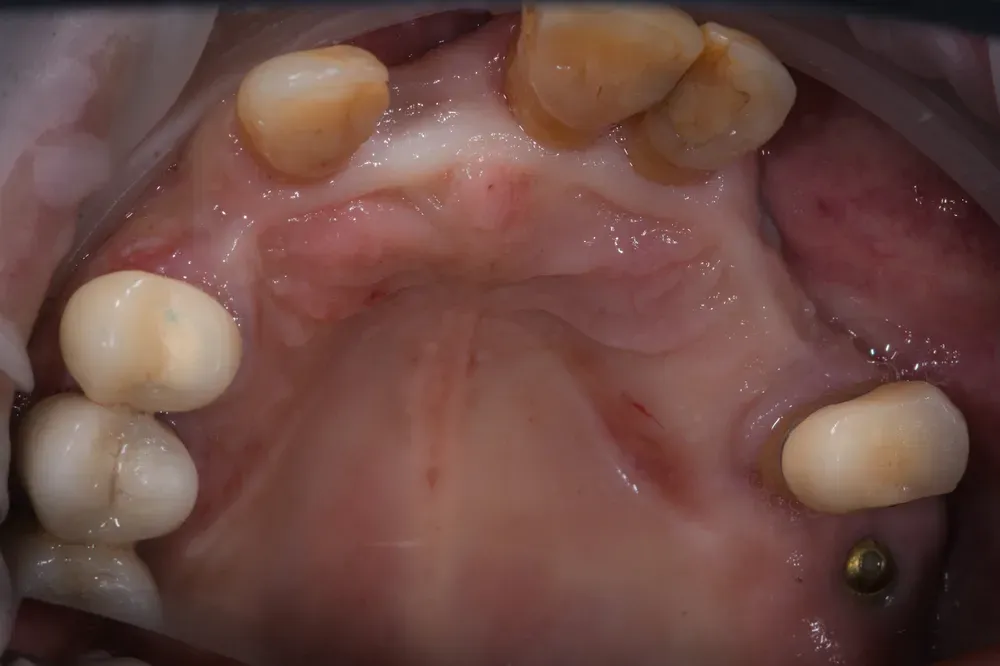

Nelle due figure sottostanti è evidente come la terapia, qui ancora in fase di estrazione dei denti non mantenibili, ottenga il ripristino totale (la rigenerazione) del tessuto alveolare e quindi una forma del tutto simile a quella naturale. E questo si ottiene solo con l’espansione mucosa del sito e senza xenoinnesti di connettivo. Inoltre, nei siti (alveoli) estrattivi non è stato inserito nulla per mantenere la forma: il mantenimento si ottiene solo con la forma del provvisorio che si inserisce per 4 mm all’interno con i “ponti ovoidi”.

Insomma la rigenerazione si ottiene con l’aria, anzi con il sangue che riempe i vuoti e poi grazie alle cellule che colonizzano i sito dai bordi e senza aggiunta di altri materiali. Bello no?

Abbiamo fatto una scansione con scanner intraorale per finalizzare il lavoro con la ceramica e, grazie ai nuovi denti che sono stati resi possibili dalla forma delle gengive che vedete nelle immagini sottostanti, egli ha ripreso la sua vita dinamica, più felice di prima, con la possibilità di godere appieno di ogni sua giornata grazie anche ai suoi nuovi denti! E lui si merita tutto ciò e anche di più: credetemi.

Come si ottiene la rigenerazione mucosa senza xenoinnesti di connettivo? Mediante la tecnica dei ponti ovoidi in un provvisorio inserito 4mm negli alveoli estrattivi, la mucosa si espande naturalmente. Il sangue riempie i vuoti iniziali e le cellule colonizzano il sito dai bordi senza aggiunta di materiali. È una rigenerazione biologica pura.